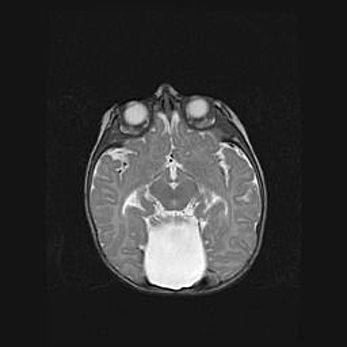

Наружная гидроцефалия с возможной атрофией височных областей.

Возраст: 28 дней

Вес: 3670 г

Пол: мужской

Окружность головы: 38 см

Срок гестации: 40 недель

Гидроцефалия головного мозга у новорожденных – это заболевание, которое характеризуется скоплением избыточного количества спинномозговой жидкости в желудочковой системе головного мозга в результате затруднения её перемещения от места выработки к месту поглощения в кровеносную систему или вследствие нарушения абсорбции. При открытой наружной форме гидроцефалии у новорожденных расширяются и переполняются субарахноидные пространства.

При нормотензивных  формах,  которые,  как  правило,  являются  следствием  перенесенных ишемических  повреждений  паренхимы  мозга,  возможно  сочетание микроцефалии  с нормотензивной гидроцефалией. В основе данных изменений лежит атрофия больших полушарий с преимущественной  локализацией  в  лобно-височных  областях.